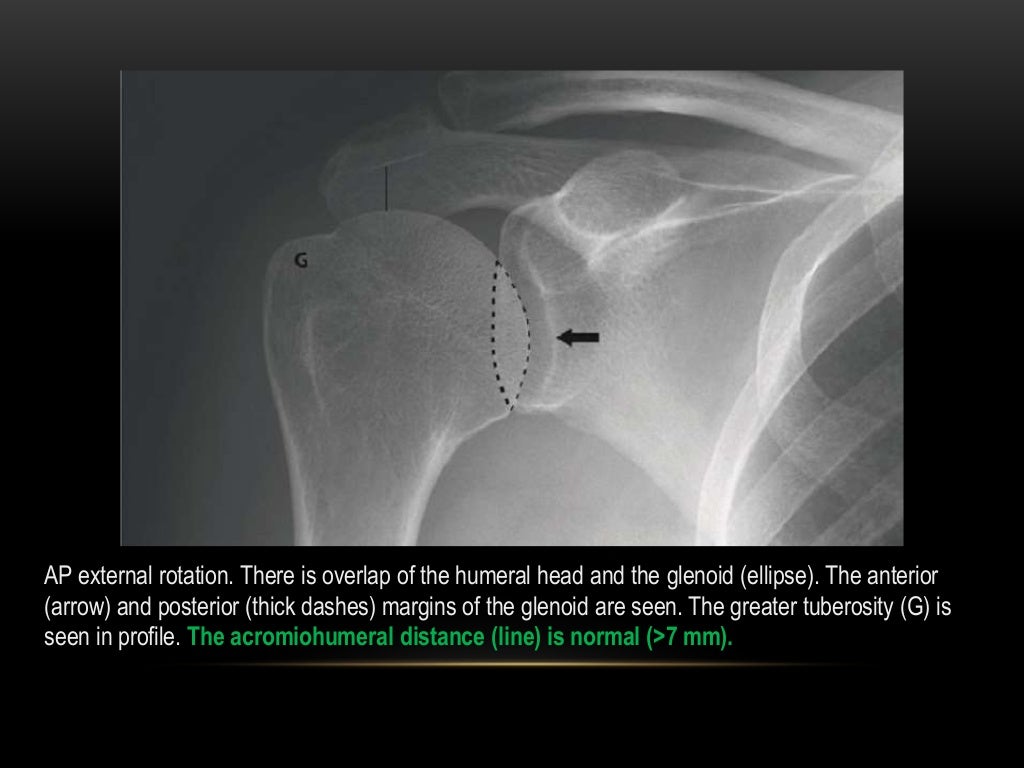

From www.slideshare.net